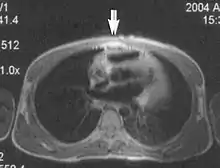

Flow can manifest as either an altered intravascular signal (flow enhancement or flow-related signal loss), or as flow-related artifacts (ghost images or spatial misregistration). Flow enhancement, also known as inflow effect, is caused by fully magnetised protons entering the imaged slice while the stationary protons have not fully regained their magnetization.[1] The fully magnetized protons yield a high signal in comparison with the rest of the surroundings. High velocity flow causes the protons entering the image to be removed from it by the time the 180-degree pulse is administered. The effect is that these protons do not contribute to the echo and are registered as a signal void or flow-related signal loss (Fig. 2).[1] Spatial misregistration manifests as displacement of an intravascular signal owing to position encoding of a voxel in the phase direction preceding frequency encoding by time TE/2.The intensity of the artifact is dependent on the signal intensity from the vessel, and is less apparent with increased TE.[1]